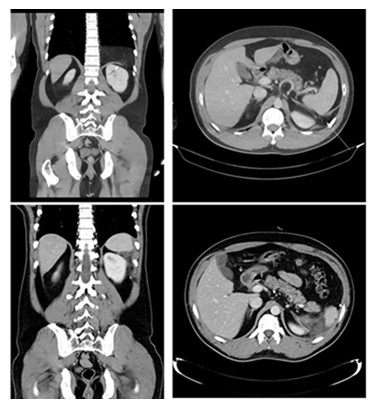

The most common presenting symptom was gastrointestinal discomfort (5/11, 45.5%), followed by chest pain (2/11, 18.2%), respiratory distress (2/11, 18.2%), and back pain (2/11, 18.2%); three patients (27.3%) were asymptomatic at diagnosis (Table 2). Computed tomography (CT) established the preoperative diagnosis in all patients, and routine postoperative CT was obtained on postoperative day (POD) 5 (POD 6 for the Bochdalek case) (Figures 4-6).

- Hiatal hernia; Pre-OP CT

- Post-OP CT (POD #5)

- Morgagni hernia ; Pre-OP CT

- Post-OP CT (POD#5)

- Bochdalek hernia ; Pre-OP CT

- Post-OP CT (POD #6)